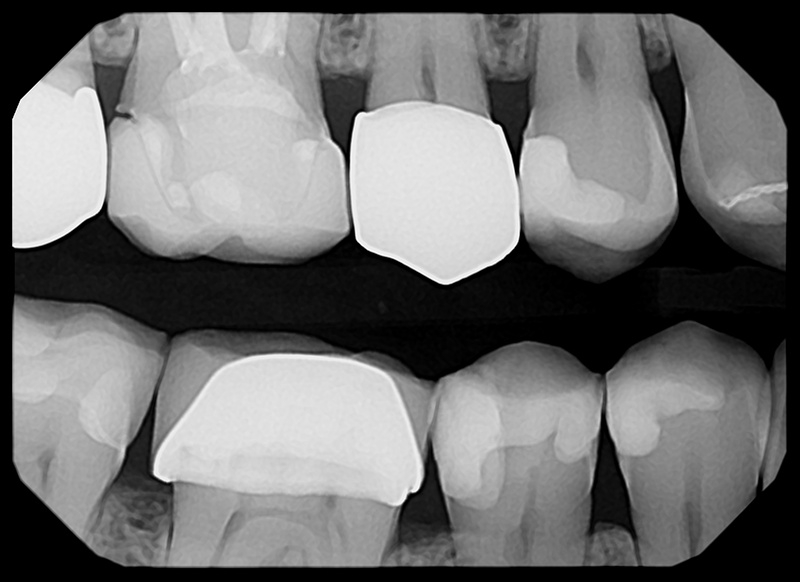

Crisp Images, Low Exposure

The low-noise design delivers exceptional clarity even at lower doses. Keeps patients safer while improving diagnostic confidence.

Capture Every Detail — High-Quality Imaging. Designed for Patient Comfort.

See The Clarity For Yourself

• Left Bitewing

• Mandibular Anterior

• Right Bitewing

• Maxillary Anterior